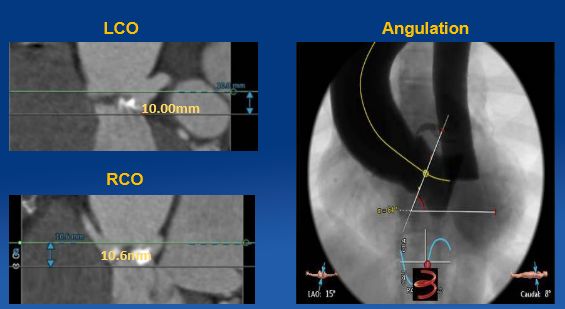

来自浙江大学医学院附属第二医院的何宇欣医师现场演示了TAVR患者术前CT的测量与分析。

通过对CT图像的三维重建及分析可以提供左心室流出道、主动脉瓣环、主动脉窦部、窦管交界及升主动脉多平面的尺寸(包括长径、短径、周长和面积),冠状动脉开口的高度及其与临近解剖结构的关系,及主动脉根部的钙化情况,指导人工瓣膜尺寸的选择、TAVR手术规划。同时CT扫描可以评估外周血管的内径、扭曲度、钙化等情况,指导手术入路的选择。通过准确的测量我们可以充分评估患者是否适合TAVR手术,并且人工瓣膜的尺寸选择及手术规划。MDCT评估结果见Figure 4~Figure 7。

Figure 4

CT评估主动脉瓣环及主动脉窦部

Figure 5

CT评估钙化形态及分布

Figure 6

CT评估冠脉开口高度及瓣环角度

Figure 7

CT评估股动脉入路